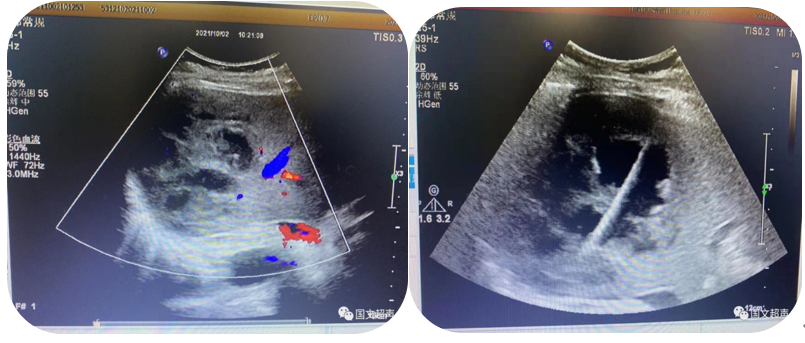

2.超聲引導(dǎo)下置管引流

超聲實(shí)時(shí)引導(dǎo)下將引流管放置在胸腹腔積液,臟器及間隙膿腫內(nèi)抽取積液減輕癥狀,亦可將藥物注入到某些特定部位從而達(dá)到治療效果。

經(jīng)皮肝膿腫穿刺引流

心包積液穿刺引流/腹腔積液穿刺引流